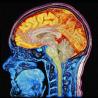

Nature:3万人大脑图像众包研究,发现基因与脑容量的关系

对遗传学家来讲,人类大脑仍然是一个谜团。但是大数据战略可以协助其破解此谜团。众多神经科学家和医生通过对3万人脑图像和DNA进行对比,得出几个基因可能会影响大脑特定区域的大小,这些区域涉及智力、记忆,同时也影响大脑本身的大小。

众包研究

人脑图像

基因

脑容量